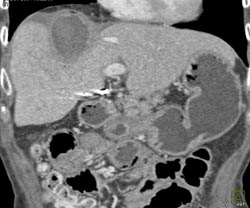

Liver Abscess